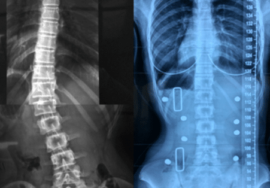

الأشعة السينية (X-ray)

تساعد على تقييم زاوية الانحناء ومدى تأثيره على القناة الشوكية.

تستخدم لمتابعة تطور الانحناء عبر الزمن.